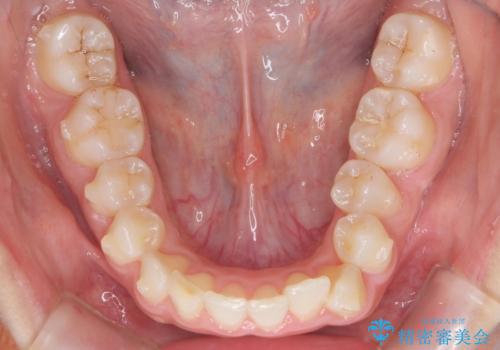

治療にも大変満足していただきました。

リファインメントも1回で済んでいます。